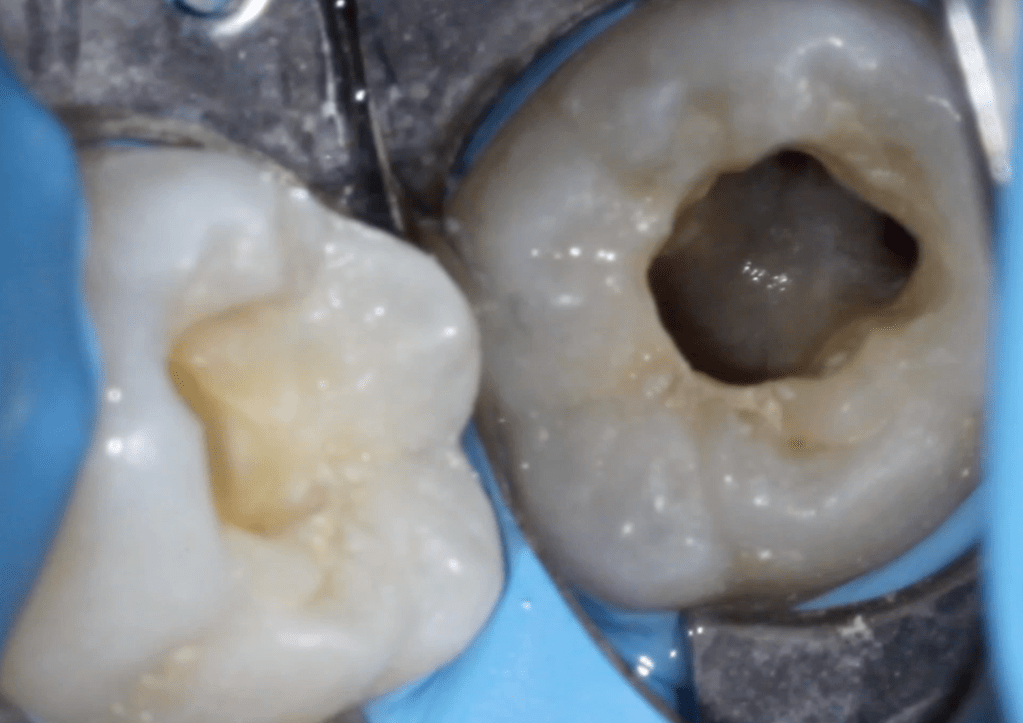

Pulpotomía biodentine + reco preendio